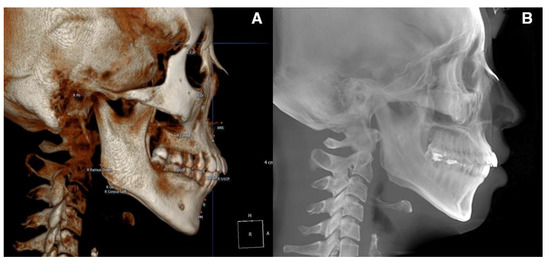

The Digital Imaging and Communications in Medicine (DICOM) files were converted into the. stl format, the standard file type representing the 3D surface geometry (Figure 3). Skeletal and soft tissue surfaces were constructed using the Invesalius open-access software (Renato Archer Information Technology Center, Campinas, Brazil). A specific density within the images that were derived from different shades of gray was customized by moving the threshold bars using an advanced 3D processing software (Geomagic Control X, 3D Systems, Rock Hill, SC, USA). An auto-alignment of the STereoLithography (STL) files obtained at T0 and T1 was performed, and the correspondence between the reference (T0) and measured (T1) data was checked (Figure 4).

Figure 4. Alignment of the pre-treatment and post-treatment surface data. (A), Before superimposition. (B), The superimposition process involved the following two steps; (i) initial alignment was performed before running other alignment types. The software automatically calculated an initial fit between the two objects to get the Reference (pre) and Measured (post) data close and register features. (ii) Best fit alignment was then applied to calculate the best fit between the two objects automatically. (C), 3D comparison function after alignment.